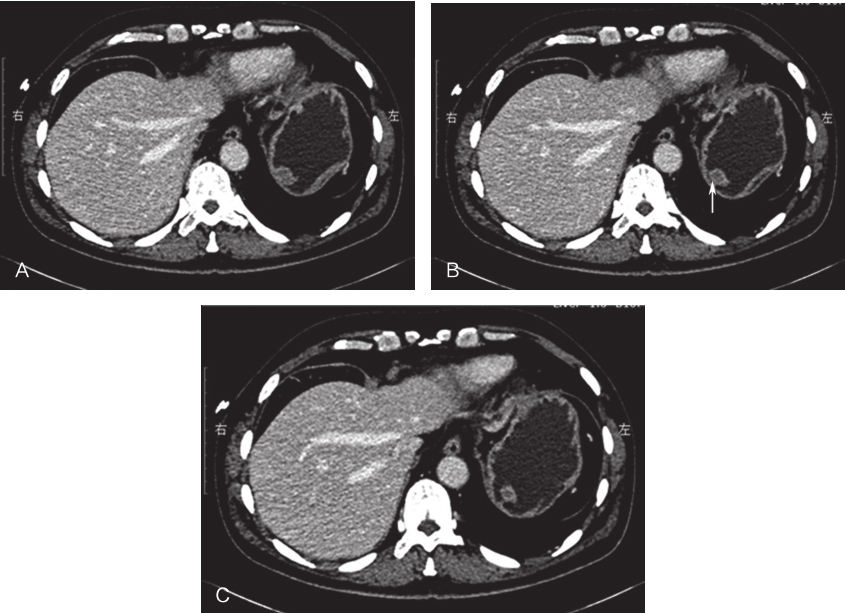

全腹增强CT:胃底软组织结节,考虑胃间质瘤可能,建议结合胃镜检查;肝顶多发小囊肿(图2)。

图2腹部增强CT